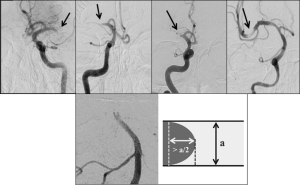

Four different angiographic patterns have been described on the initial angiogram, at the interface between the proximal end of occluding thrombi and the patent arterial segment4,5 (Fig. 1, upper panel):

- Cut-off appearance: abrupt interruption of contrast, without generating any specific shape.

- Tapered appearance: gradual luminal narrowing, forming an acute angle over the superior/inferior vessel wall.

- Meniscus appearance: abrupt interruption of contrast delineating a concavity towards the proximal lumen.

3.1 Claw-sign appearance6: variation of the meniscus occlusion, in which the protrusion length of the contrast on each side of the thrombus convexity was more than half of the parent vessel diameter (Fig. 1, lower panel).

- Tram-track appearance: a partially occlusive lesion, with visible distal contrast filling the lumen and several pieces of thrombotic material serially positioned. The extended linear contrast can be observed on one or both arterial walls.

Fig 1: Upper panel, from left to right: Cut-off, tapered, meniscus and tram-track occlusion patterns. Reproduced with permission from Pr. Ashfaq Shuaib, Department of Medicine (Neurology), University of Alberta, Edmonton, AB, Canada; Lower panel: ‘Claw-sign’ positive occlusion pattern with contrast protrusion length on each side estimated at more than half of the parent vessel diameter. Reproduced with permission from Dr. Yuki Yamamoto, Department of Clinical Neuroscience, Institute of Biomedical Sciences, Tokushima University, Tokushima, Japan.